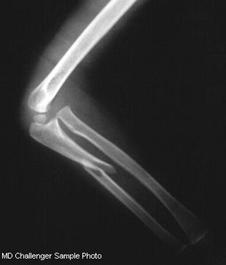

Fractura Monteggia Fractura 1/3 proximala radius si ulna Fractura proximala intracapsulara

de humerus

Luxatie

gleno-humerala

Fractura proximala

intracapsulara de humerus Fractura proximala intracapsulara de humerus

gleno-humerala Luxatie gleno-humerala